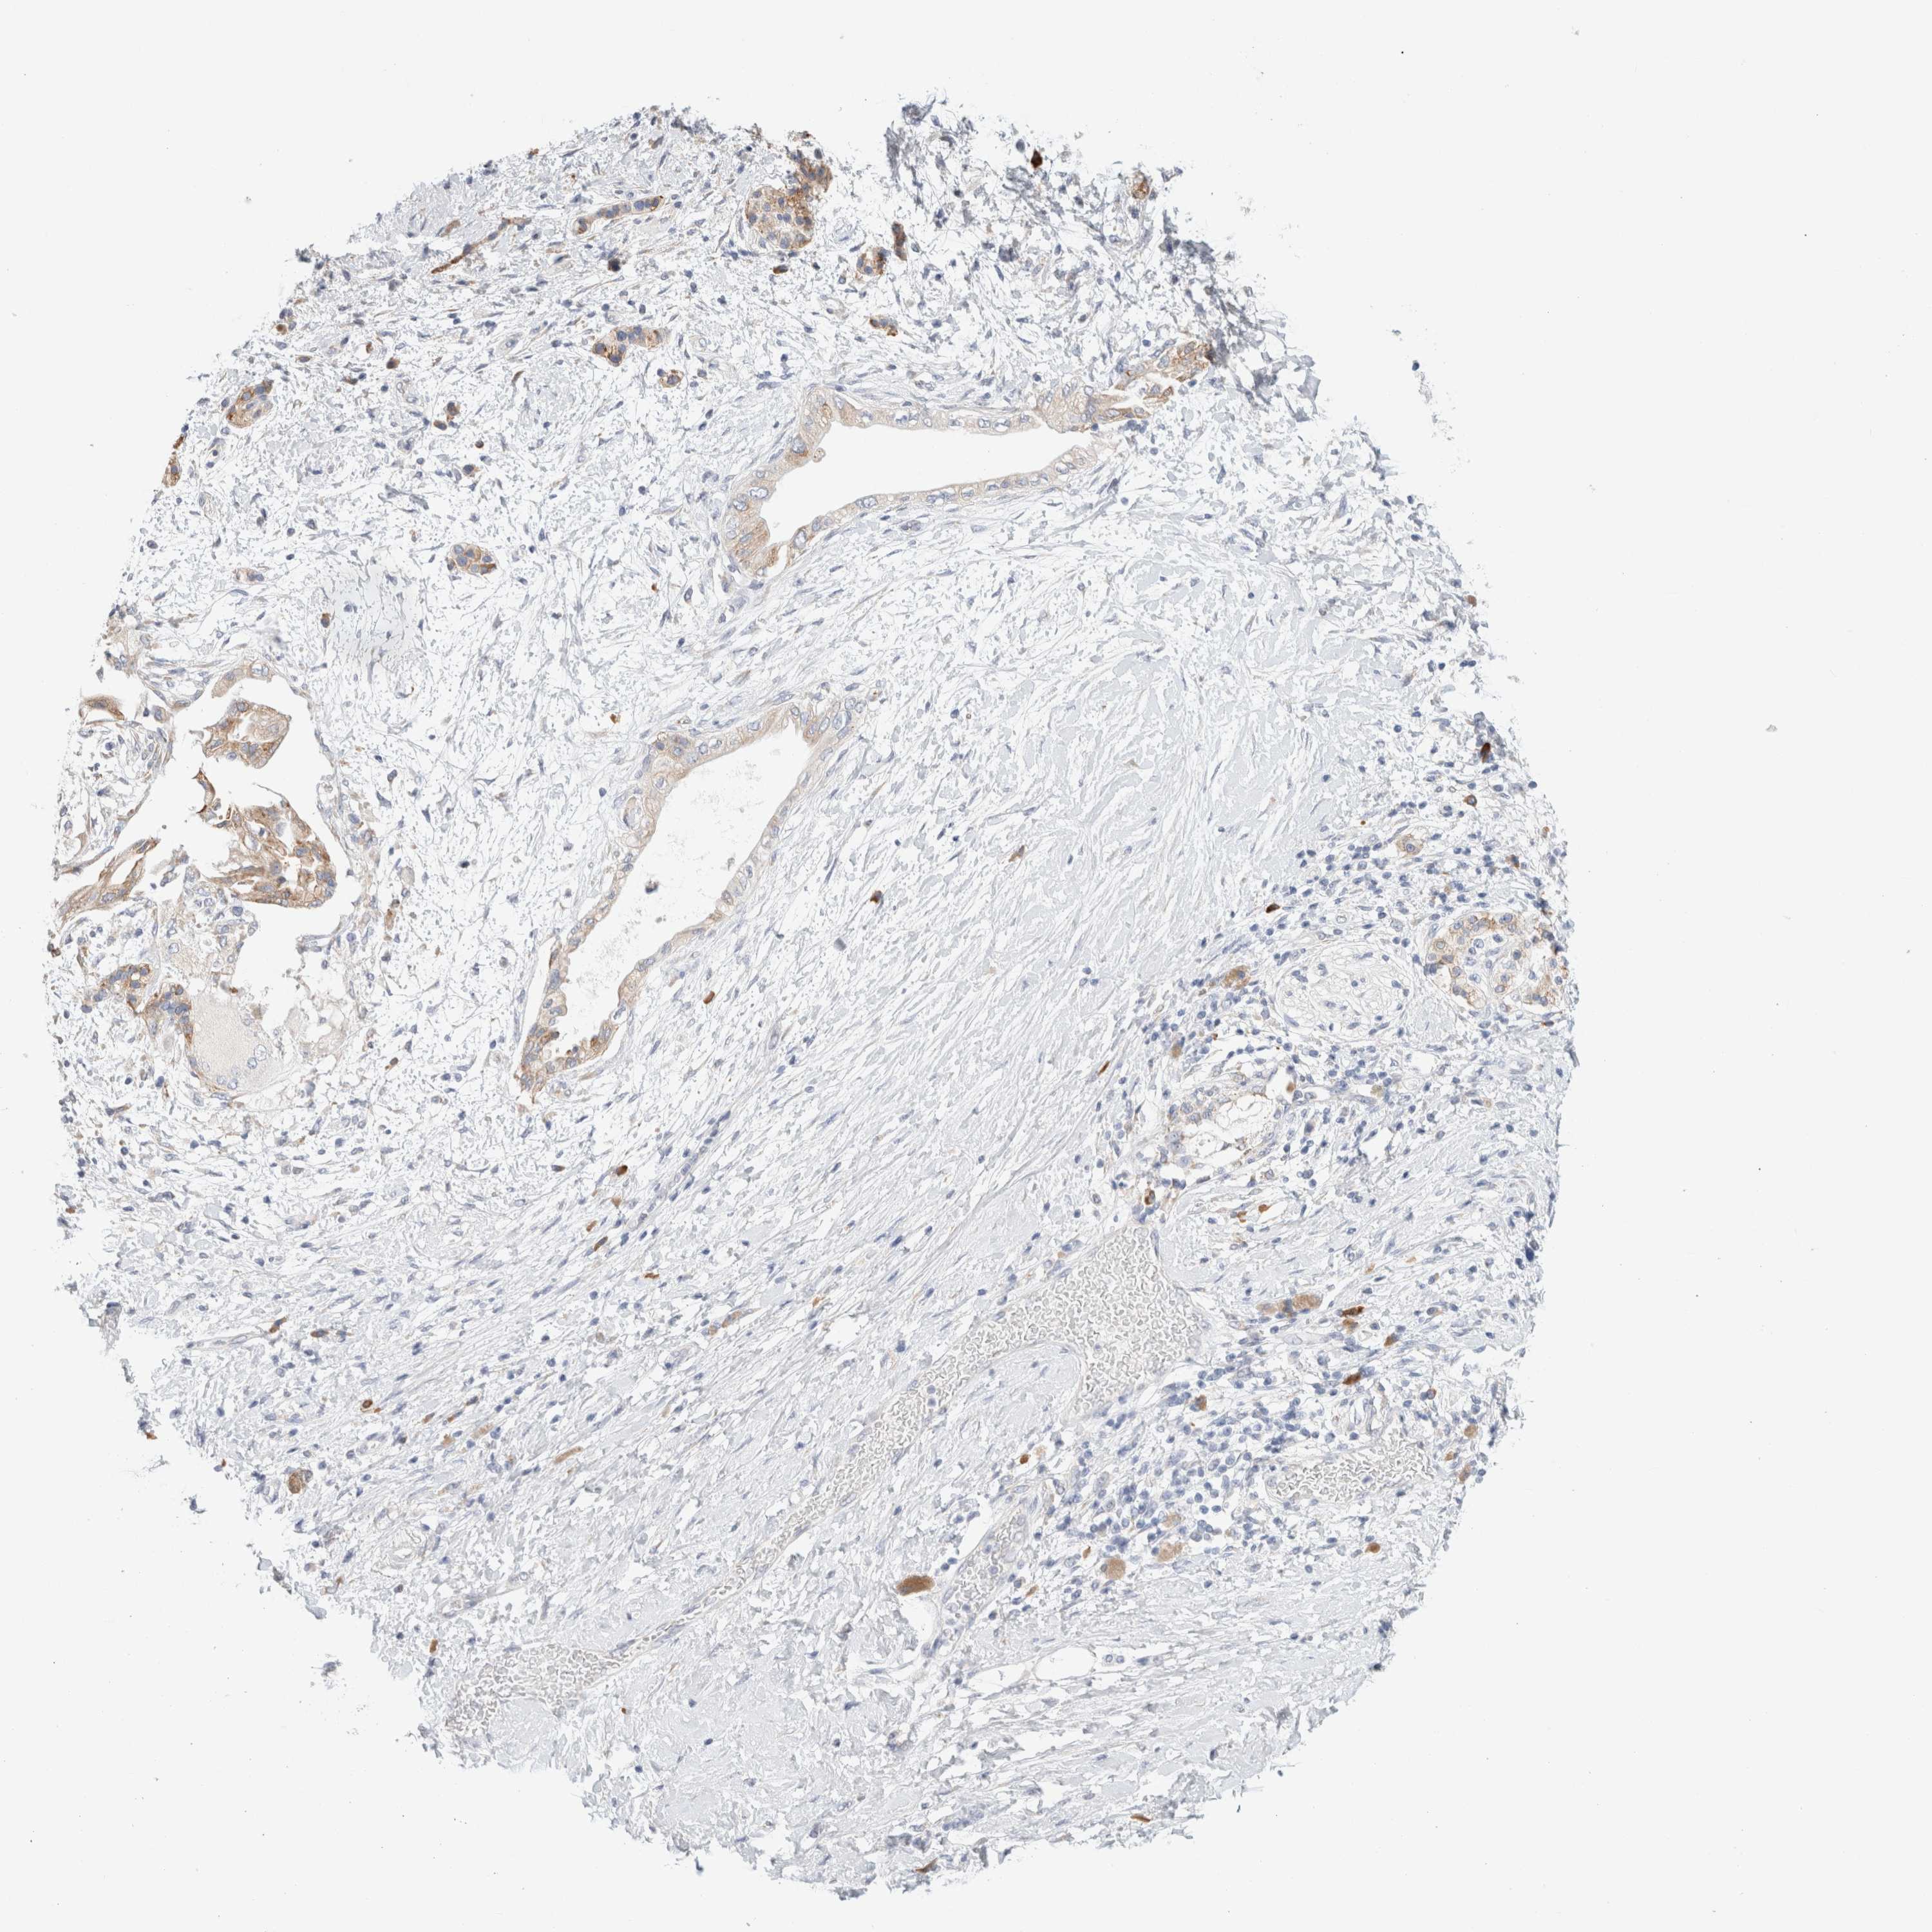

PANCREATIC CANCER - Protein expressioni

A mouse-over function shows sample information and annotation data. Click on an image to view it in a full screen mode. Samples can be filtered based on level of antibody staining by selecting one or several of the following categories: high, medium, low and not detected. The assay and annotation is described here.

Note that samples used for immunohistochemistry by the Human Protein Atlas do not correspond to samples in the TCGA dataset.

Antibody stainingi

Antibody staining in the annotated cell types in the current human tissue is reported as not detected, low, medium, or high, based on conventional immunohistochemistry profiling in selected tissues. This score is based on the combination of the staining intensity and fraction of stained cells.

Each image is clickable and will lead to virtual microscopy that enables deeper exploration of all samples and also displays staining intensity scores, fraction scores and subcellular localization as well as patient and tissue information for each sample.

Antibody HPA026488

Antibody HPA028425

Antibody CAB011203

Staining

High

Medium

Low

Not detected

Intensity

Strong

Moderate

Weak

Negative

Quantity

>75%

75%-25%

<25%

None

Location

Nuclear

Cytoplasmic/membranous

Cytoplasmic/membranous,nuclear

Adenocarcinoma, NOS

Adenocarcinoma, metastatic, NOS